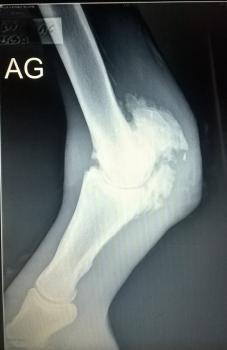

boulet cassé